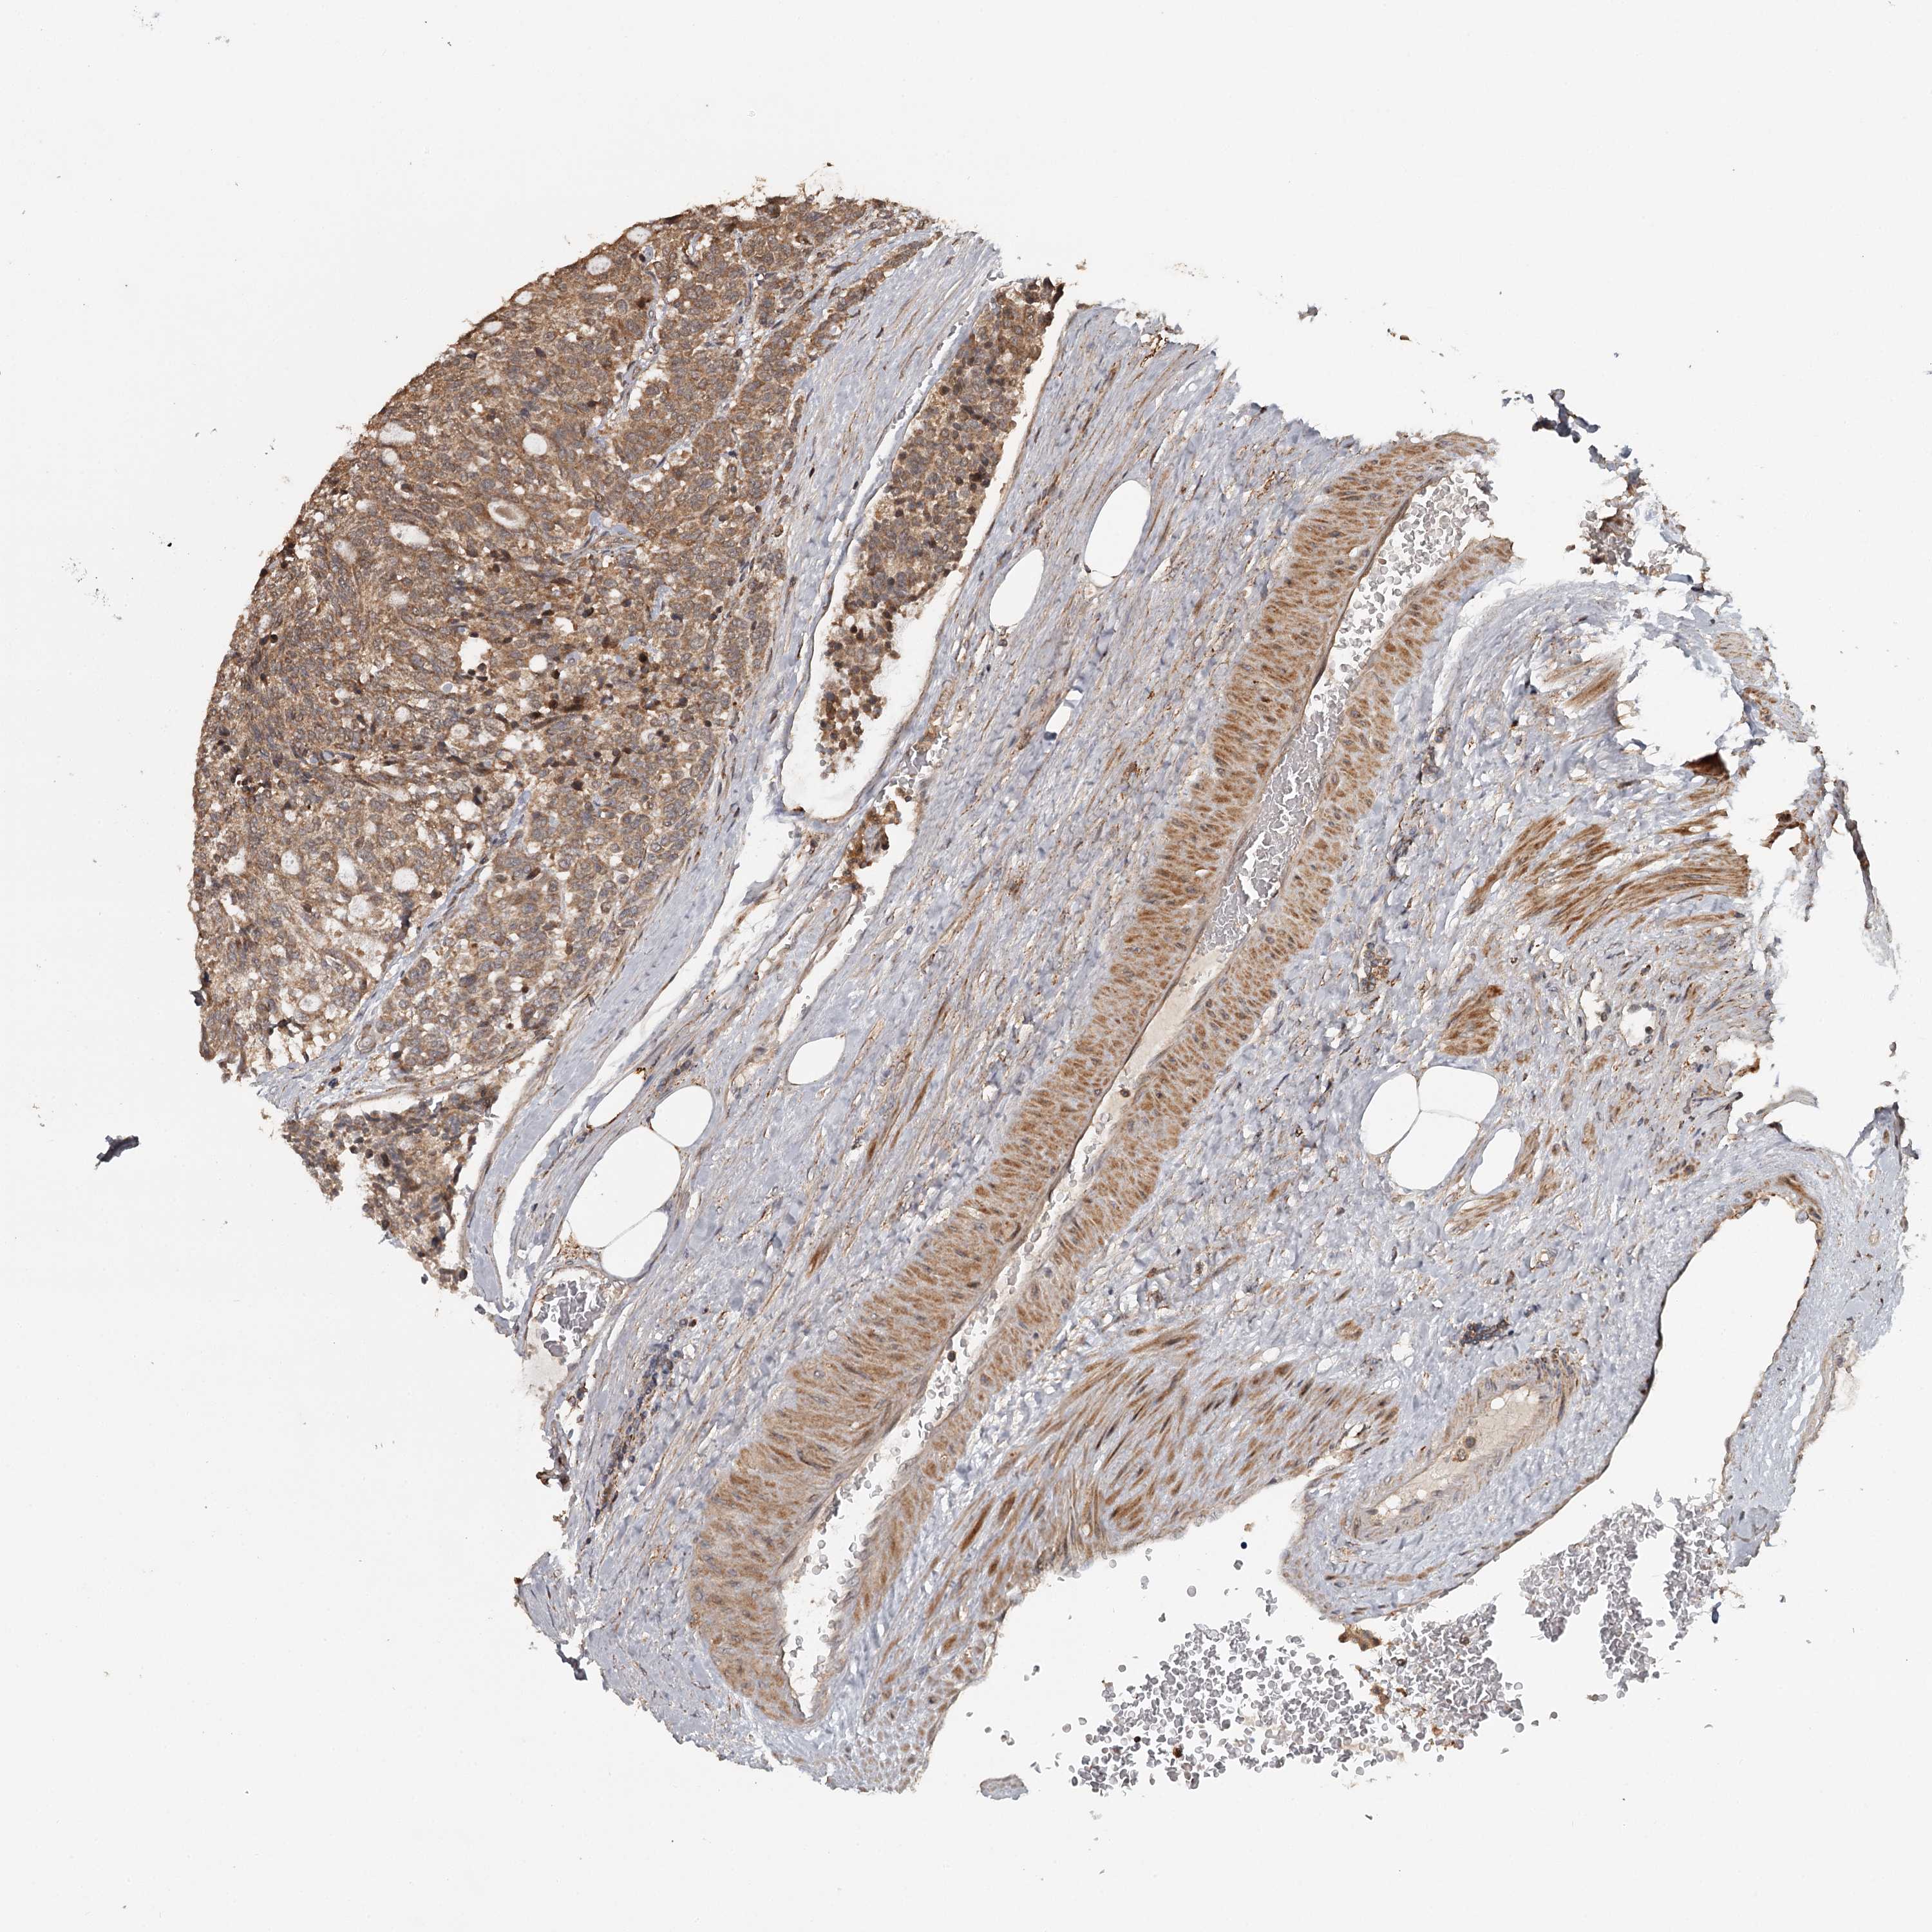

CARCINOID - Protein expressioni

A mouse-over function shows sample information and annotation data. Click on an image to view it in a full screen mode. Samples can be filtered based on level of antibody staining by selecting one or several of the following categories: high, medium, low and not detected. The assay and annotation is described here.

Antibody stainingi

Antibody staining in the annotated cell types in the current human tissue is reported as not detected, low, medium, or high, based on conventional immunohistochemistry profiling in selected tissues. This score is based on the combination of the staining intensity and fraction of stained cells.

Each image is clickable and will lead to virtual microscopy that enables deeper exploration of all samples and also displays staining intensity scores, fraction scores and subcellular localization as well as patient and tissue information for each sample.

Antibody HPA039106

Staining

High

Medium

Low

Not detected

Intensity

Strong

Moderate

Weak

Negative

Quantity

>75%

75%-25%

<25%

None

Location

Nuclear

Cytoplasmic/membranous

Cytoplasmic/membranous,nuclear

Carcinoid, malignant, NOS

Carcinoma, NOS